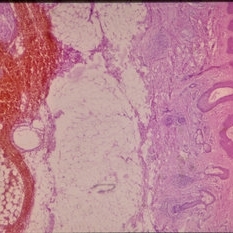

Histopathology of Linear Sebaceous Nevus Syndrome

Histopathology of Linear Sebaceous Nevus Syndrome

Feb 20 2015 by H. Michael Lambert, MD

Histopathology of linear sebaceous nevus syndrome.

Condition/keywords: histopathology, linear nevus sebaceous syndrome